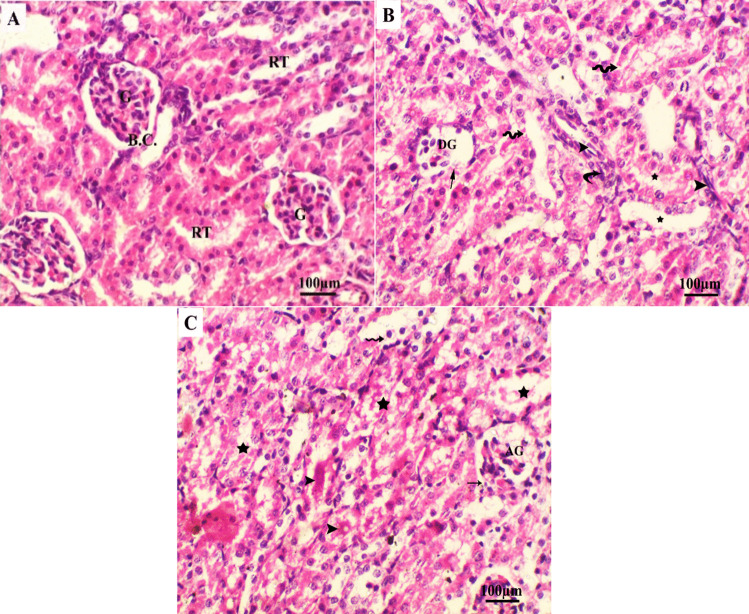

Lactational exposure to antibacterial medications may affect the normal development of newborns during this crucial stage and later in adult life. Linezolid (LNZ) is an oxazolidinone antibacterial drug that is effective against drug-resistant Gram-positive bacteria and multidrug-resistant Mycobacterium tuberculosis. Although it is relatively toxic, there is insufficient data about LNZ use during lactation. This study aimed to elucidate the impact of linezolid administration during lactation on Wistar rats' offspring. Eighteen lactating Wistar female rats were separated into three groups (n = 6): control, therapeutic, and low dose groups. The therapeutic dose group received 61.66 mg/kg of LNZ (equivalent to the human dose), while the low dose group received 15.41 mg/kg of LNZ (1/4 of the human therapeutic dose) by gavage twice daily. All lactating dams and their offspring died four days after receiving a therapeutic dose. In the low dose group, LNZ significantly reduced the body weight of lactating females and their pups. The liver tissue of the pups showed a considerable increase in malondialdehyde levels, along with a decrease in the catalase, glutathione, and superoxide dismutase activities accompanied by moderate histological alterations like congestion, and infiltration, and DNA fragmentation as indicated by comet assay. Microscopic examination of renal tissue revealed glomeruli deterioration, cellular infiltration, and intratubular protein deposits. In conclusion, this study highlights the potential risks linezolid may pose to infants during postpartum. Therefore, there is a need for preweaning monitoring and caution should be taken during breastfeeding.